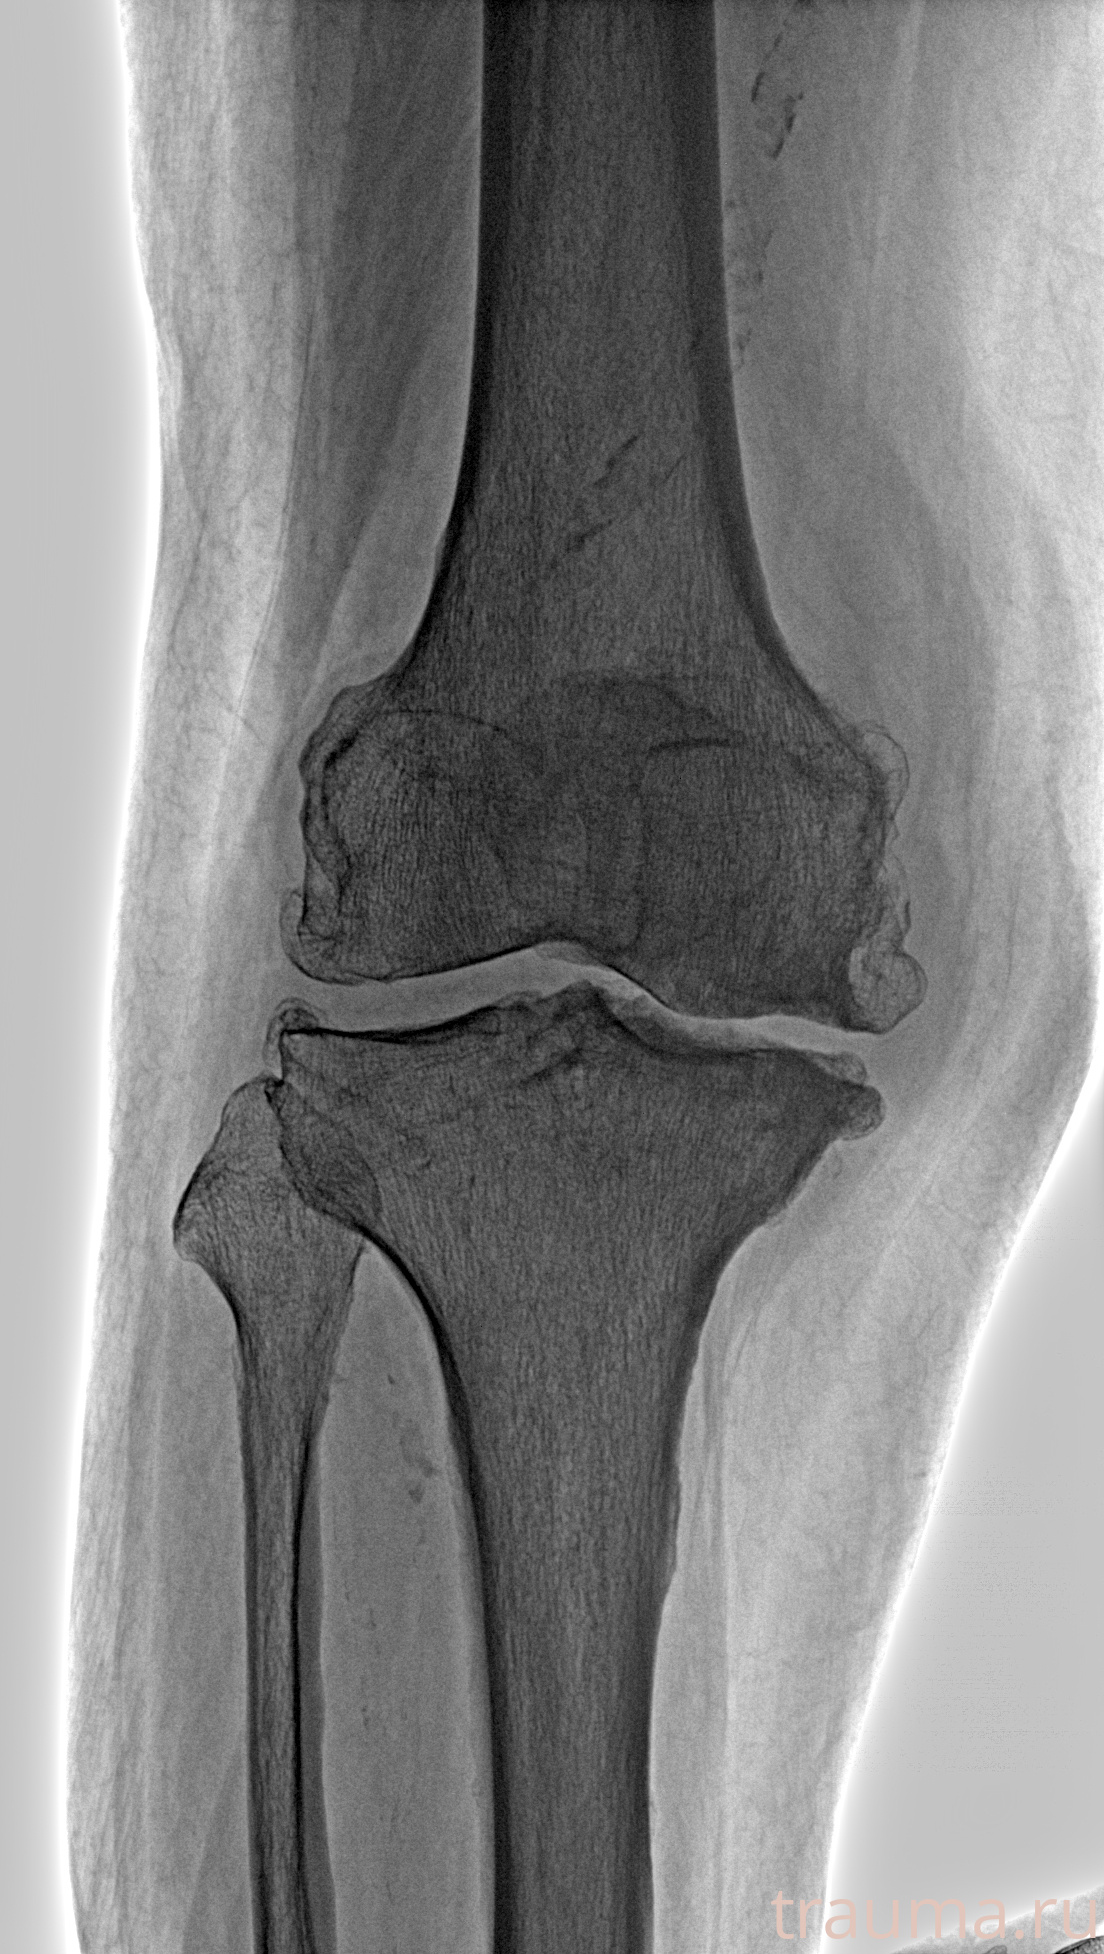

Рентгенограммы

Рентген на дому: по вашему адресу приезжает врач-рентгенолог, травматолог-ортопед с мобильным рентгеновским аппаратом, проводит диагностику травмы или заболевания, делает необходимые рентгенограммы, дает рекомендации по дальнейшему лечению. Получить качественные снимки в домашних условиях возможно благодаря уникальной методике, разработанной МосРентген Центром для института  Склифосовского